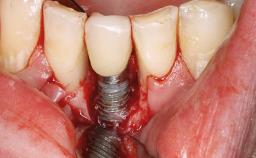

Peripheral Giant-cell Granuloma Associated with Peri-implant Tissues

Placement Protocol Early or late implant placement